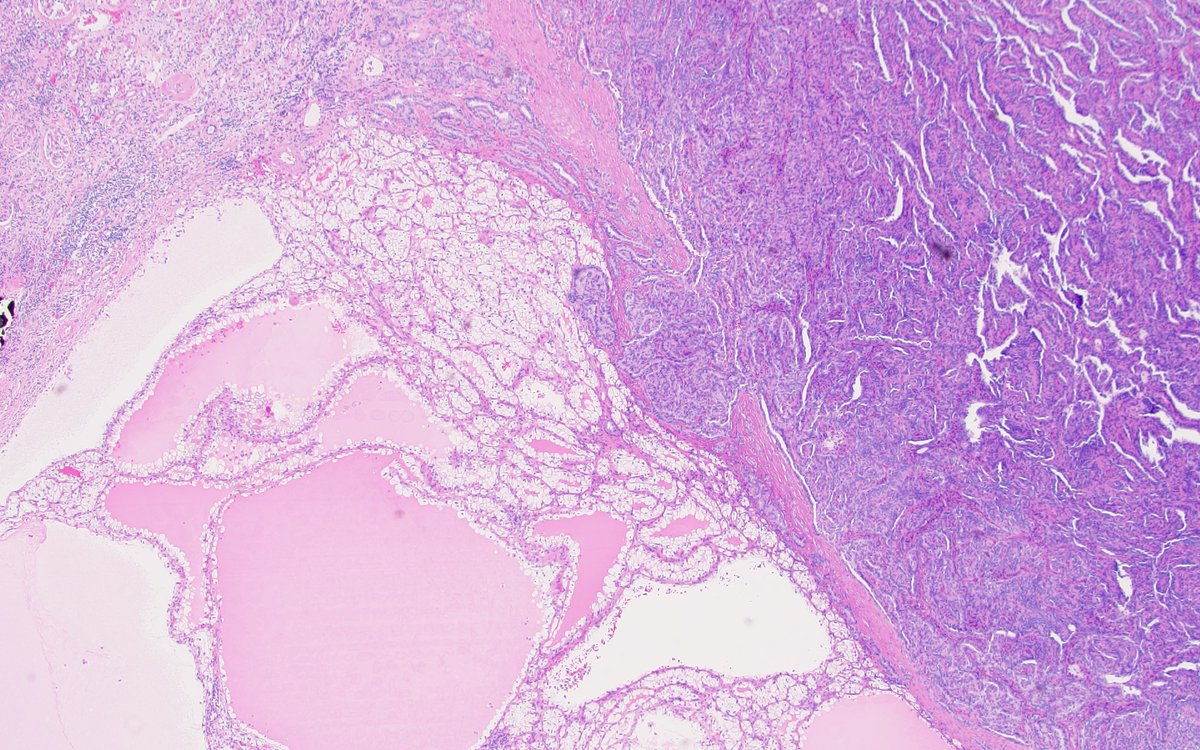

Collision of clear cell renal cell carcinoma and papillary renal cell carcinoma! This #prcc is trying to invade #ccrcc! #PathTwitter #gupath